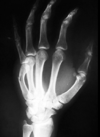

97

¿Qué tipo de Rx se hace en fx de falanges y qué tipo se hace en fx de metacarpianos?

- Falanges: AP y latera - Metacarpianos: AP y oblicua

98

# Fractura de falanges Hacer TC en caso de ______ y hacer RM para buscar ______

- TC en caso de duda - RM para buscar lesión ligamentaria/tendinosa